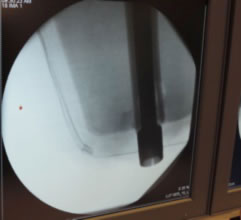

The reported clinical experience has shown that the implant can be securely fixed into the medullary canal of the distal residual femur. This stable fixation is achieved by preparation of the femur with reamers and precision cutting instruments prior-to implantation.

Figure 8. Modeling with IM rod checking length, diameter and curvature. |

Current software is now available to aid in preparation, planning while guiding the production of your custom device, along with planning your surgery.

Custom fabrication can then be on sound scientific demonstration of fit and fill of the required parameters to ensure proper fit of the device.